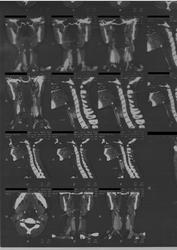

Пациентка 33 года,обратилась с жалобами на чувство инородного тела в гортани,наличие  "кома в горле"в течение 2 х лет.Причину не указывает.Ранее не лесилась.Беременность 5-6 нед. Обследована:эндоскопия ЖКТ без потологии,Лор патологии не выявлено,ФОГ в норме,УЗИ щитовидной железы без патологии. КТ для обсуждения.

2 года "ком в горле", а КТ во время беременности. Даже не забавно... Стрелками указано накопление контраста в язычной миндалине. Скорее гипертрофия+обострение воспаления.

Как гипертрофию язычной миндалины ).Причем ЛОР не видит этой патологии.(В заключении норма).Дама ,к сожалению,согласие не подписывала,и беременность сохранять не будет.Диагноз не установлен.